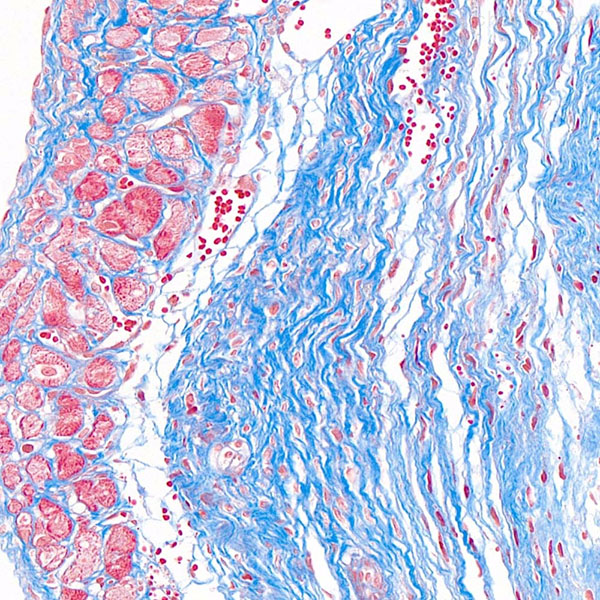

Masson染色